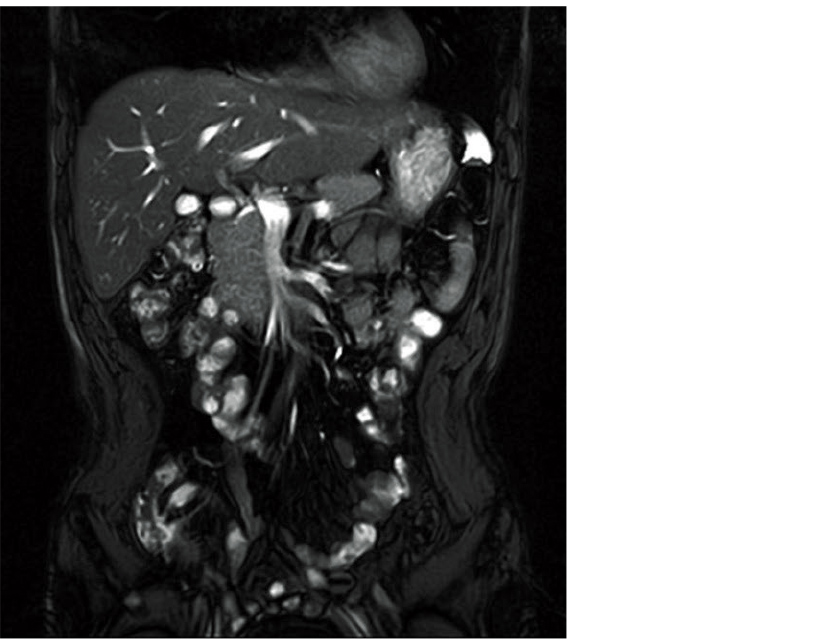

VASC-ASL is a non-contrast imaging method that can visualize fast blood flow in the renal artery and portal vein in the abdomen. This feature visualizes blood flows labelled with IR pulses using the 3D BASG sequence and does not require ECG/pulse wave synchronization.

Selectively applying IR pulses upstream in the blood vessels to be visualized and acquiring images when the blood flow is Null enables the incoming labelled blood flow to be visualized as Black Blood. Therefore, by capturing images twice with selective IR pulses ON and OFF and acquiring a subtraction image, blood flows labelled with IR pulses will be visualized as a high-intensity area.

Examples of VASC-ASL images